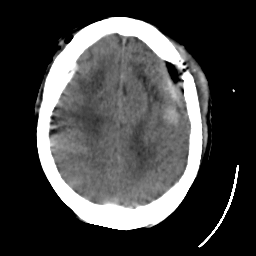

Meningioma: Roentgen-ray CT #1 -- Slice #16

[Home][Help][Clinical] Slice 16